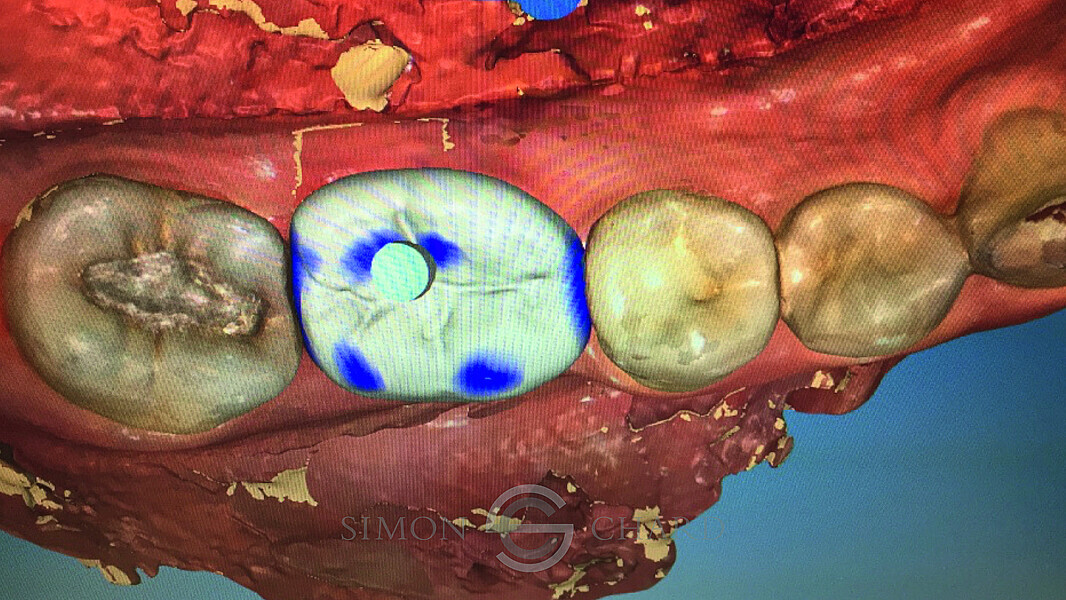

Implant restoration with CEREC